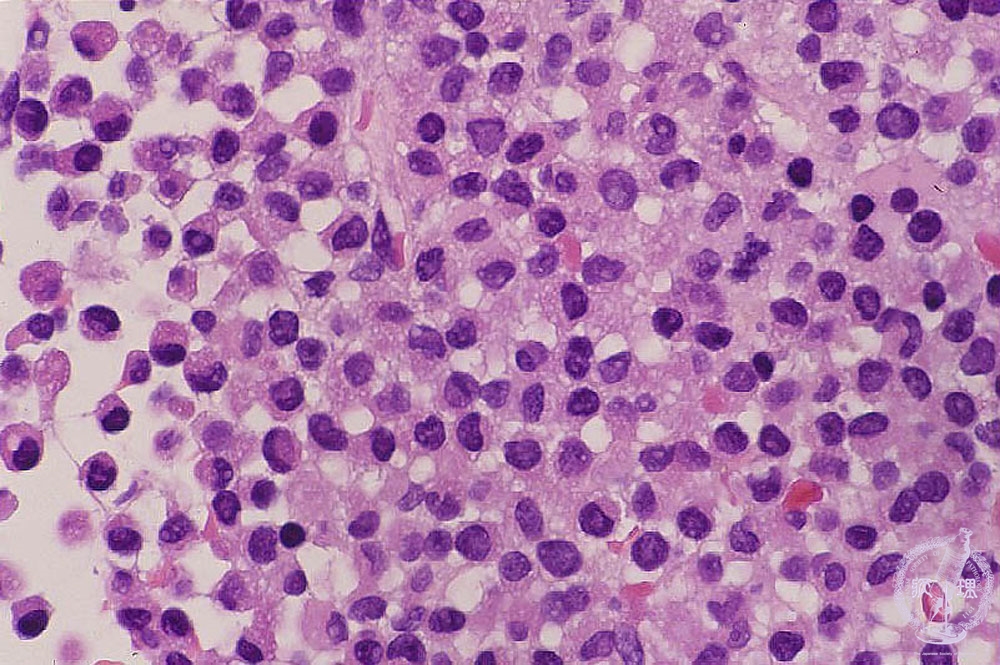

- š(5) Acute myeloid leukemia(M3)

Microscopic image (H&E high power view): Acute promyelocytic leukemia (M3). Diffuse proliferation of myeloblasts is found. This type of leukemia sometimes form green nodules, therefore it was called as gchloromah. Notoriously, it often causes disseminated intravascular coagulation (DIC).